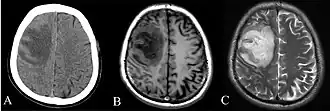

Various imaging modalities can also help with the diagnosis of melioidosis. In acute melioidosis with the spreading of the bacteria through the bloodstream, the chest X-ray shows multifocal nodular lesions. It may also show merging nodules or cavitations. For those with acute melioidosis without the spread to the bloodstream, chest X-ray most commonly shows upper lobe consolidation or cavitations.[10] In chronic melioidosis, the slow progression of upper lobe consolidation of the lungs resembles tuberculosis.[10] For abscesses located in other parts of the body apart from the lungs, especially in the liver and spleen, CT scan has higher sensitivity when compared with an ultrasound scan. In liver and splenic abscesses, an ultrasound scan shows "target-like" lesions while a CT scan shows "honeycomb sign" (abscess with loculations separated by thin septa) in liver abscesses.[10] For melioidosis involving the brain, MRI has higher sensitivity than a CT scan in diagnosing the lesion. MRI shows ring-enhancing lesions for brain melioidosis.[10]